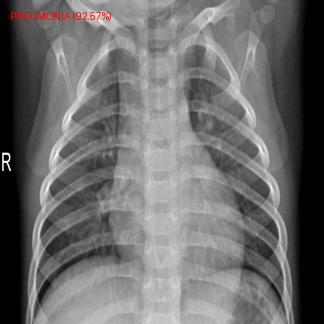

This project uses the DenseNet121 model to detect pneumonia in chest X-ray images. The model is trained on a dataset with train, validation, and test splits from kaggle and demonstrates the use of transfer learning and data augmentation in PyTorch.

The model uses DenseNet121, a pre-trained model available in torchvision.models. Its final layer is replaced with a fully connected layer for binary classification.